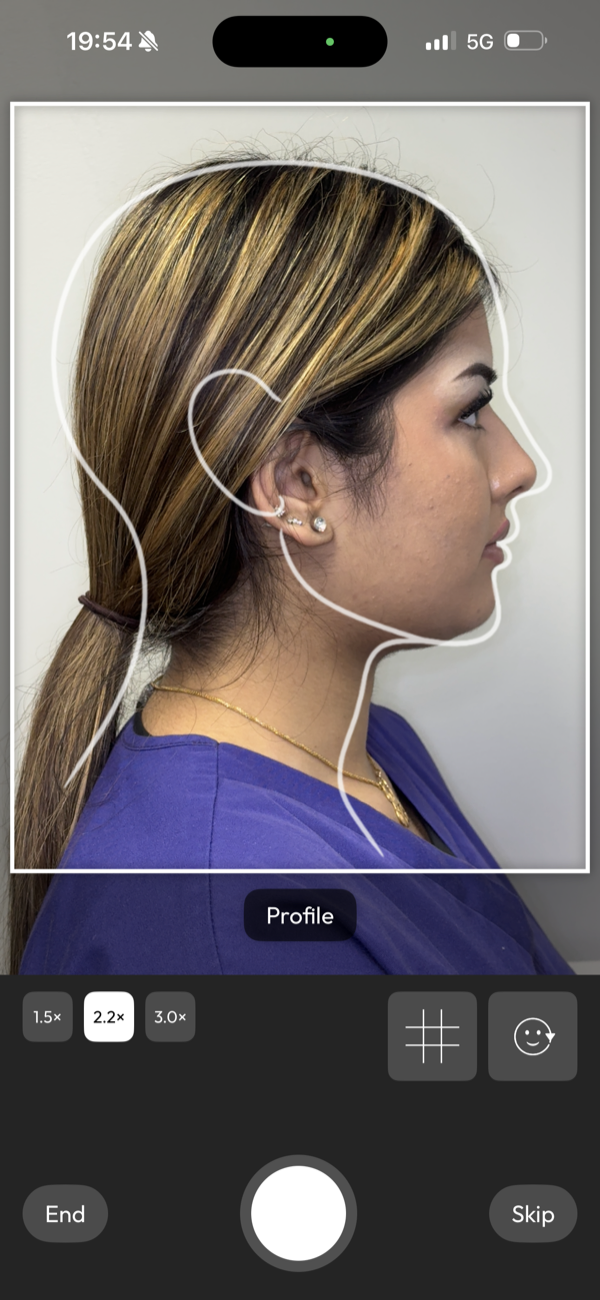

picture perfect images

Capture images with guided precision or import your DSLR work, then transform them into flawless before-and-after cases ready to present and share.

Will phone photos be good enough?

Yes, in most cases.

Modern phone cameras, used with appropriate lighting, are well suited to clinical photography. DentalFolio's guided capture additionally supports consistent framing and orientation. DSLR images can also be imported if preferred.